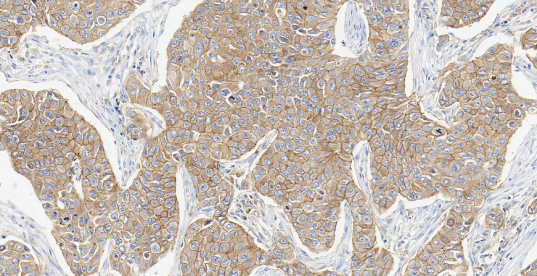

PR

PR——孕激素受体,属于核激素受体超家族。

• 定位:细胞核。

• 功能:孕激素受体是一种核内转录因子,当与孕激素结合后,主要调控子宫内膜向分泌期转化及平衡雌激素驱动的乳腺增生。

PR 表达依赖完整 ER 信号通路。在 ER 阳性的乳腺癌中,PR 阳性进一步证实了激素信号通路的活跃性,是预测内分泌治疗反应性的重要辅助指标,通常与更好的预后和更高的内分泌治疗有效率相关[8]。

图 5. 人乳腺癌组织的 PR 免疫组化分析。